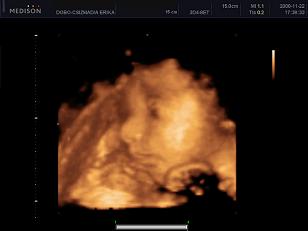

Kép 31+2 hét